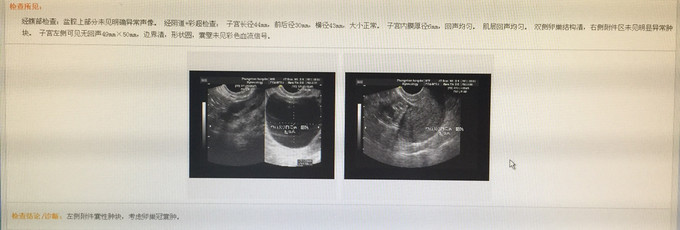

患者因“发现盆腔包块4年”入院。患者2011年体检时B超提示附件囊肿,大小约3cm,定期复查囊肿无明显增大。今年9月7日我院复查B超提示“左附件囊性肿块50*49mm,考虑卵巢冠囊肿。为进一步诊治入院。